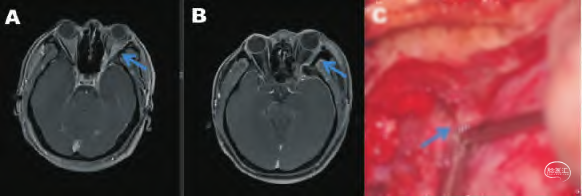

眼眶内脑膜瘤切除,眶-翼点入路

A.术前;B.术后;C. 术中采用匙形刀头行硬膜外前床突切除